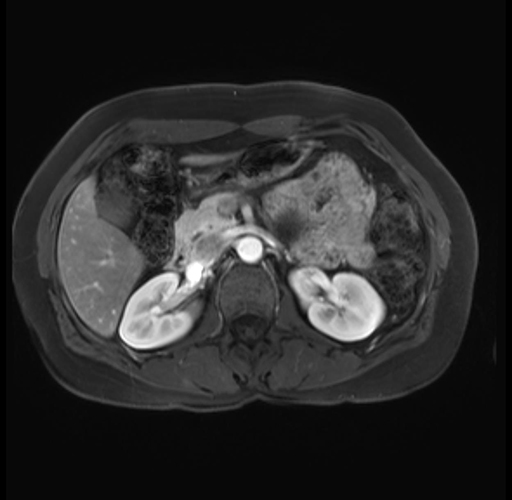

Imaging Analysis

Look through the patient's CT scan to identify any areas of concern for the necessary procedure.

Based on your CT findings, which issue(s) are present and would give reason for "planned slowing down moment(s)" in this case?